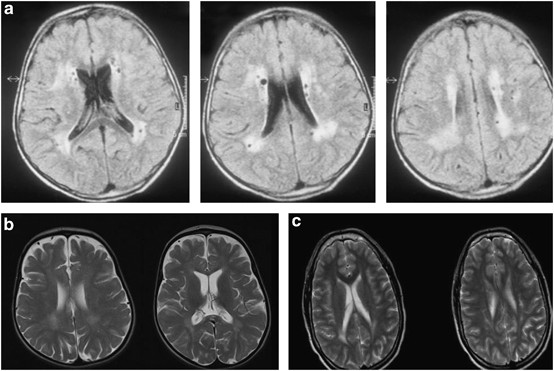

Cranial MRI in patient 1 at the age of 18 years showed cerebral atrophy. The gyration was normal. There were bilateral, cystic-gliotic, parietal periventricular white matter abnormalities observed (Figure 3a). The pontocerebellar structures and the corpus callosum were normal, and no abnormalities of the basal ganglia were present. Patients 3, 4 and 6 had partial dysgenesis of the corpus callosum. MRI in patient 5 revealed cerebellar vermis hypoplasia and a thin corpus callosum. In patient 6, cranial CT imaging showed severe cerebral atrophy, abnormal frontal gyration (polimicrogyria) and agenesis of the corpus callosum. Patients 9, 10, 12 and 13 had a frontotemporal cobblestone-like dysgenesis (Figure 4). MRI in patient 14 revealed mild periventricular white matter changes, besides cortical atrophy from the age of 10 years (Figure 3b). Patient 15 had only minimal, nonspecific periventricular white matter changes at the age of 16 years (Figure 3c). The cranial MRI of patient 16 at the age of 6 years was normal. Patients 2 and 7 had no specific MRI abnormalities, only variable degrees of cortical atrophy. A summary of the MRI findings is given in Table 1.

White matter anomalies in patients diagnosed with RIN2 and GORAB mutations. (a) Axial FLAIR images of patient 1 diagnosed with MACS syndrome at the age of 18, showing periventricular white matter disease with cystic lesions in the white matter. The U fibers are spared. (b, c) Mild white matter changes in the periventricular white matter and in the corpus callosum on axial T2 images in patients 14 and 15 at age of 10 and 16 years, diagnosed with GO syndrome, intellectual disability and spasticity.